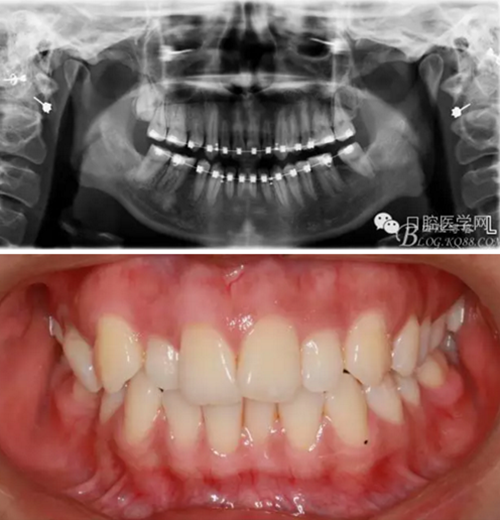

37,45缺失后,鄰牙近中移動(dòng)占據(jù)了部分牙位;患者要求減少治療費(fèi)用,不做種植修復(fù),那怎么協(xié)調(diào)右側(cè)的咬合關(guān)系?

15是根管治療過(guò)的牙齒,只好忍痛舍去......

在滿足功能的前提下,退而求其次...有時(shí)候,正畸醫(yī)生不得不妥協(xié)。